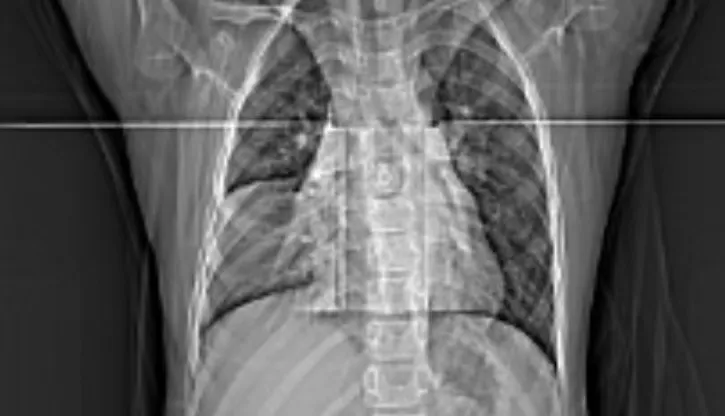

时间回到2025年12月31日这一天,儿童呼吸重症内分泌科刘平定主任团队接诊了一名5岁10个月的患儿。患儿已发热4天,胸部影像学检查显示,孩子患上了大叶性肺炎,且右肺中叶出现严重肺实变——这意味着该部分肺组织彻底失去气体交换功能,如同“沉睡”的实心块,也正是孩子持续高烧的关键原因。常规治疗手段收效有限,患儿病情亟待干预。

为明确病因并实施针对性治疗,团队当机立断决定开展支气管镜检查。当支气管镜抵达患儿右肺中叶时,镜下景象令人揪心:负责通气的内侧段、外侧段支气管开口,已被黏稠的炎性分泌物和痰栓完全封堵,看不到一丝缝隙——这就是导致肺实变的“元凶”。